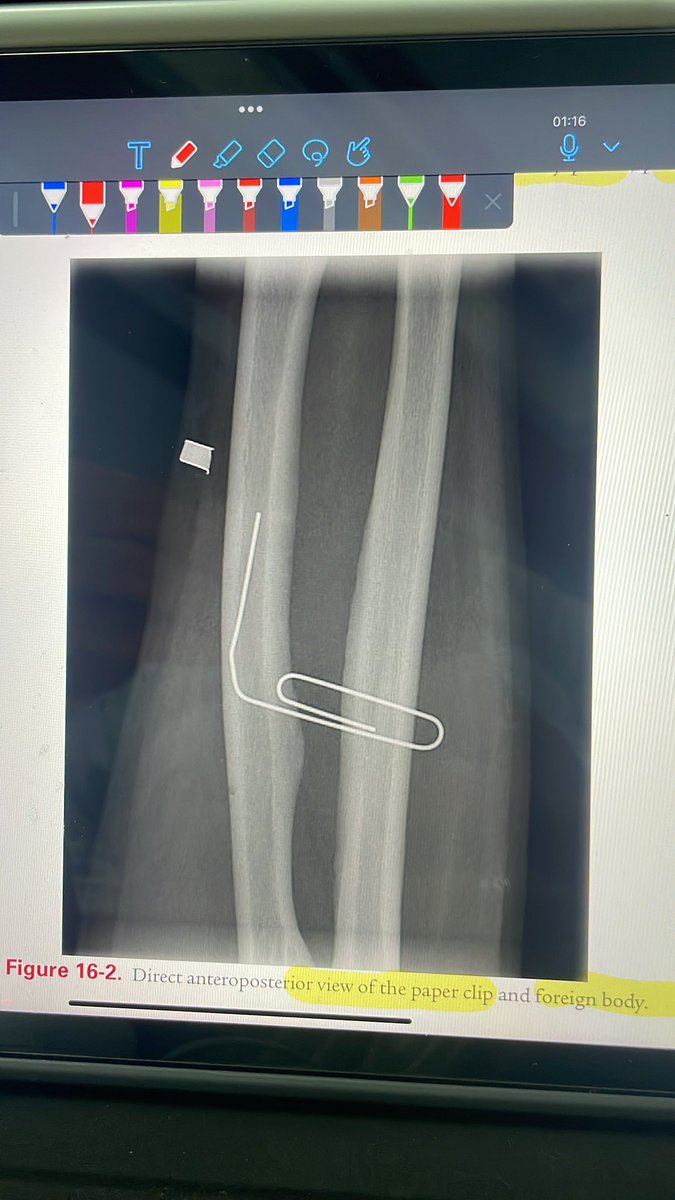

3- الاجسام الغريبة (foreign body):

ممكن يدخل الجرح اجسام مثل الزجاج او اي شيء آخر و غالباً نقوم بعمل اشعة عادية (x-ray) اذا كان فيه زجاج ممكن يبان بنسبة 95% والباقي اننا نشوف الجرح كويس قبل ما نقفله ونوقف النزيف ونتأكد إن مافيه شيء داخل عشان ما يصير التهاب في المنطقة.